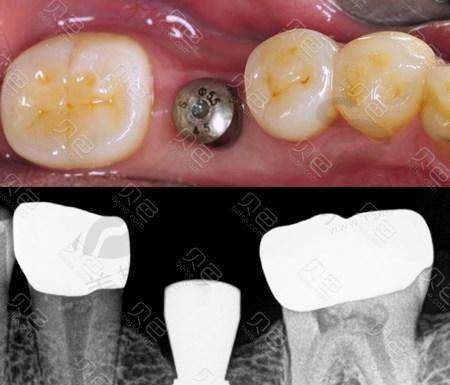

風險三:種植體鬆動(返工一族更驚!)

症狀:種好嘅牙齒搖搖晃晃,食硬嘢(如蘋果、堅果)時痛,仲有異味。

原因:「骨結合」失敗,可能因為植體材料差(非醫用鈦合金)、患者骨質太疏鬆(骨密度T值< - 2.5),或者術後太早咬硬物(有啲姊妹做完兩週就去食麻辣火鍋,結果植體移位!)。

香港數據:根據《香港牙科雜誌》2024年報告,種植體5年失敗率約2.8%,但深圳某些診所因為用「即刻負重」技術(當日種牙當日裝牙冠),失敗率高達8%,所以返工趕時間嘅姊妹千祈唔好貪快!